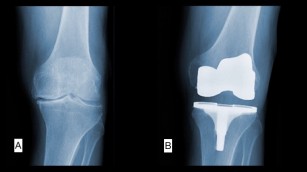

Tipuri de proteze de genunchi. Este o proteza modulara adaptabila oricarei morfologii anatomice. Proteza de genunchi de revizie permite efectuarea de revizii a unor proteze implantate anterior degradate in conditiile in care exista defecte osoase majore sau pierderi de capital osos. Artroplastia totală de genunchi presupune înlocuirea cartilajului articular degradat de la nivelul celor trei compartimente ale genunchiului cu o proteză de genunchi. O proteza partiala este folosita pentru a inlocui doar partile afectate ale genunchiului in timp ce o proteza totala presupune inlocuirea completa a genunchiului.

Astfel in majoritatea cazurilor se poate utiliza proteza totala cu trei compartimente cimentata sau necimentata cu platou tibial fix sau mobil iar in alte situatii se pot alege protezele partiale cu un compartiment care pot si de asemenea cimentate sau. Proteza totală de genunchi. Reprezinta tipul cel mai frecvent folosit de proteza de genunchi. în unele cazuri ar putea fi necesară o grefă osoasă transplantare de os din altă parte a corpului sau de la un donator pentru a susține noua proteză.